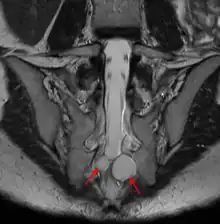

![]() | |

| MRI image showing a Tarlov cyst | |

MRI, or Magnetic Resonance Imaging, is considered the imaging study of choice in identifying Tarlov cysts. MRI provides better resolution of tissue density, absence of bone interference, multiplanar capabilities, and is noninvasive. Plain films may show bony erosion of the spinal canal or of the sacral foramina. On MRI pictures, the signal is the same as the CSF one.